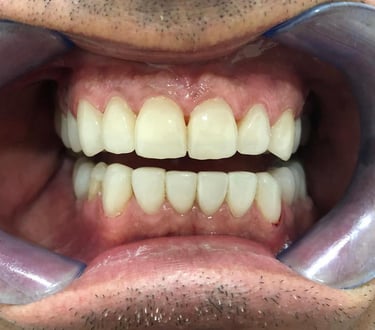

NUESTROS CASOS REALES